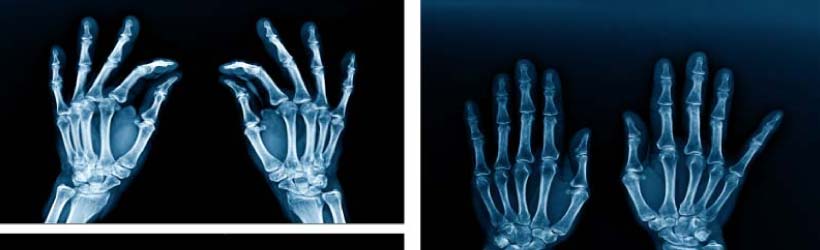

Au niveau des os, des fractures, de l’arthrose, des malformations.